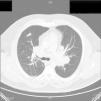

Six months after withdrawing the anti-TNF treatment because of the diagnosis of sarcoidosis, we observed a radiological improvement (Fig. 3) with a marked decrease in the size of the lymphadenopathies, and a complete blood count within normal limits.